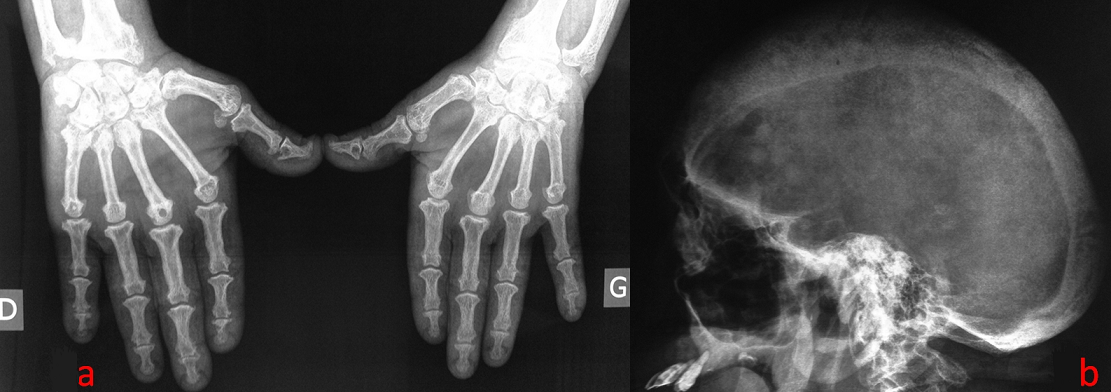

Here we report a case of 49-year-old Tunisian man followed at our consultation for bone pain. He complained of enlargement of the hands and feet since the age of 23. End stage renal failure secondary to hypertension and diabetes was discovered at the age 39. He was also operated at this age for a synchronous GH- and prolactin-secreting pituitary macroadenomas. The examination shows a frontal boss associated with macroglossia. In biology: normocalcemia at 2.16 mmol/l (normal range, 2.1-2.6 mmol/l), normophosphatemia at 1.2 mmol/l (normal range, 0.8-1.5 mmol/l) and increased alkaline phosphatase level of 4647 IU/l (normal range, 42-160 IU/l). Parathyroid hormone was increased (2788 pmol/l (normal range 100-300 ΒΌg/ml in hemodialysis patients)) as well as growth hormone (122 ng/ml (normal range, < 5 ng/ml)). 25-OH vitamin D was normal (32 ng/ml (normal range, 30-70 ng/ml)). X-rays of the hands (A) and the lateral X-ray of the skull (B) combine images of hyperparathyroidism and acromegaly. An MRI of the brain found after administration of gadolinium a recurrence of the pituitary macroadenoma. Cervical ultrasound showed a single parathyroid adenoma. The patient was referred to neurosurgeons and head and neck surgeons.